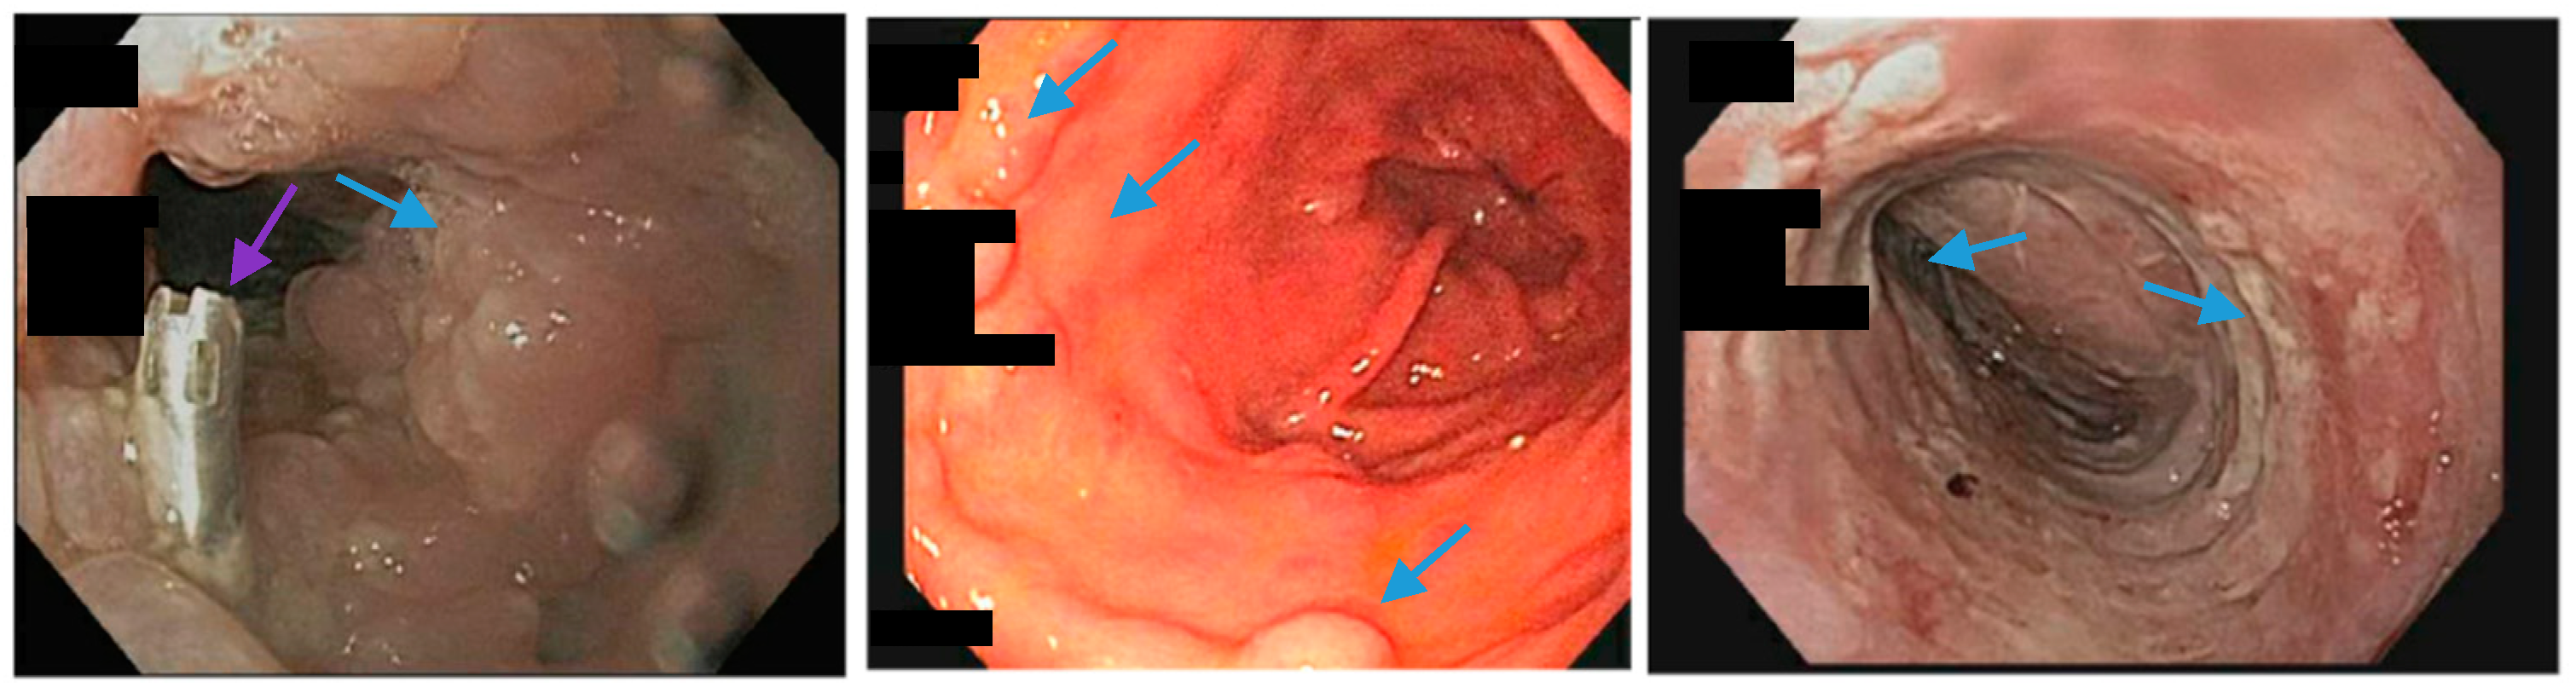

Upper endoscopy reveals an inflammatory mucosal reaction (blue arrows; left, middle and right) following the removal of a partially covered, esophageal self-expandable metal stent used for the treatment of a staple line leak in a patient with a sleeve gastrectomy. The patient reported severe regurgitation and chest pain associated with the stent. A through-the-scope clip (purple arrow, left) was used to anchor the removed stent.

Upper endoscopy reveals the proximal (blue arrows, left) and distal edge (blue arrows, middle) of a fully-covered esophageal self-expanding metal stent anchored by two through-the-scope clips (blue arrows, right) and an over-the-scope clip (green arrows, right). Note copious saliva collected around the non-peristaltic prosthesis.